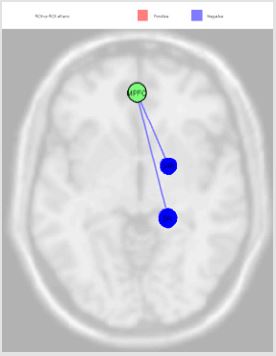

Figure 5: RLP source was directly correlated with Auditory Cortex (right) (beta 0.19; p=0.04) and Insula Cortex (left) (beta 0.06; p=0.04).

The activation of LLP source, reported in the Figure 4, was inversely correlated with Premotor Cortex (left), Dorsolateral Prefrontal Cortex (right) and Retrosplenial Cingulate Cortex (right), and directly with Primary Visual Cortex V1 (left); the MPFC source was inversely correlated with Somatosensory Associative Cortex (right) and Anterior Entorhinal Cortex (right); the PCC source was directly correlated Anterior Cingulate Cortex (right), Anterior Cingulate Cortex (left), Subcentral Area (right), Somatosensory Associative Cortex (left) and Dorsal Anterior Cingulate Cortex (right); RLP source was directly correlated with Auditory Cortex (right) and Insula Cortex (left) Figure 5. Finally, we report the MPFC connections revealed in our experiments Figure 6.

Figure 6: The MPFC source was inversely correlated with Somatosensory Associative Cortex (right) (beta -0.10; p=0.01) and Anterior Entorhinal Cortex (right) (beta -0.10; p=0.03).